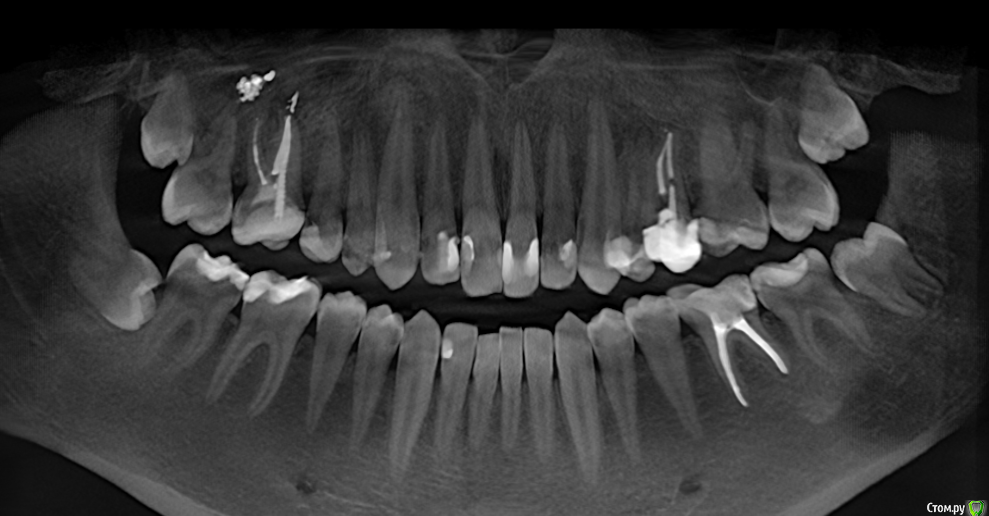

Lewsigh Опубликовано 26 декабря, 2016 Поделиться Опубликовано 26 декабря, 2016 Представленный снимок был сделан три месяца назад. Нового, к сожалению, нет. Речь идет о 48 зубе. Нижнюю восьмерку с противоположной стороны, которая начала прорезаться, уже удалил. Удаление 48-го назначено на 14 февраля в бесплатной стоматологии (но у чудесного хирурга). Зуб лежит перпендикулярно относительно семерки.Подскажите, пожалуйста, продержится ли семерка еще полтора месяца? Начал сильно беспокоиться по этому поводу, т.к. за последние две недели усилился хруст и щелчки с правой стороны при открытии рта, начал ощущать давление 8-ки на челюсть. Боюсь, что она очень быстро растет и я могу лишиться седьмого зуба. Стоит ли уже сейчас бежать и удалять её в платную стоматологию? Ссылка на комментарий

Lewsigh Опубликовано 26 декабря, 2016 Автор Поделиться Опубликовано 26 декабря, 2016 (изменено) Тут наблюдается маленький запас. Но это было три месяца назад. Изменено 26 декабря, 2016 пользователем Lewsigh Ссылка на комментарий